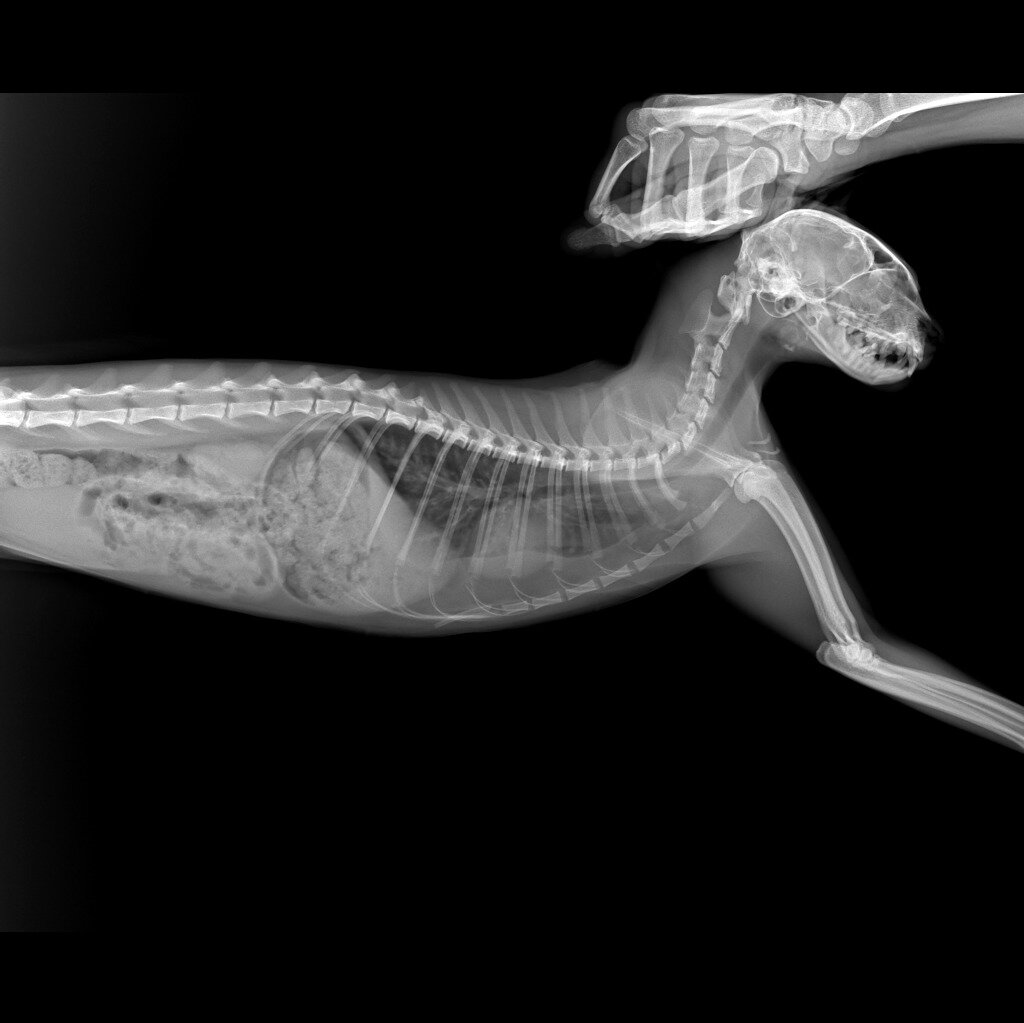

Друзья, 22.03. носила двух кошек и одного котика на кастрацию в ветклинику" Умка". Одна из них была Кобра. Она ко мне попала в ноябре 23 г-тяжело дышала, задыхалась. Рентген показал, что у кошки был сильный ушиб грудной клетки, в легких жидкость на уровне паха кровавое мессиво. Кошечка прошла длительное леченик, а попутно и пережила холода в тепле и безопасности. У кошечки всё было хорошо, но меня смущал периодический надрывный сильный кашель. Сделали ей повторный рентген и была запланирована кастрация. В кастрации нам отказали (пока), потому что кошечка во время введения наркоза может уйти на Радугу. Хорошо, что я ее не глистогонила всё это время. Меня смущал кашель, а т к у меня уже были сердечники, такую процедуру нужно делать очень аккуратно или можно потерять кошечку.

Рентгеновский снимок показал патологию сердца. По снимку видно, что сердце лежит на легком, так не должно быть. Врожденная или приобретенная патология, пока сказать не можем. А в последние дни приступы кашля участились, что меня пугает. Предварительный диагноз - подозрение на патологию сердца и астму. Кошечке назначено пройти УЗИ сердца. В понедельник ее запишем на обследование. Запись за 2-3 недели.